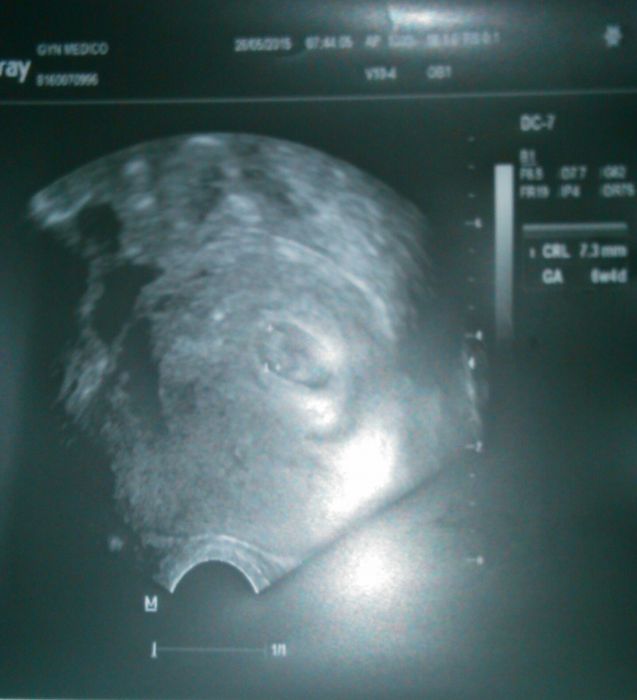

vcera jsem tu zjistovala, kdy jste ktera videla srdicko, protoze doktorka minule nic nevidela a vystrasila me, ze se broucek nevyviji....

Dnes jsem byla na kontrole a srdicko tluce jak dive, broucek je uplne v ooradku, jen asi o tyden mladsi, nez vychazi z vypoctu :)